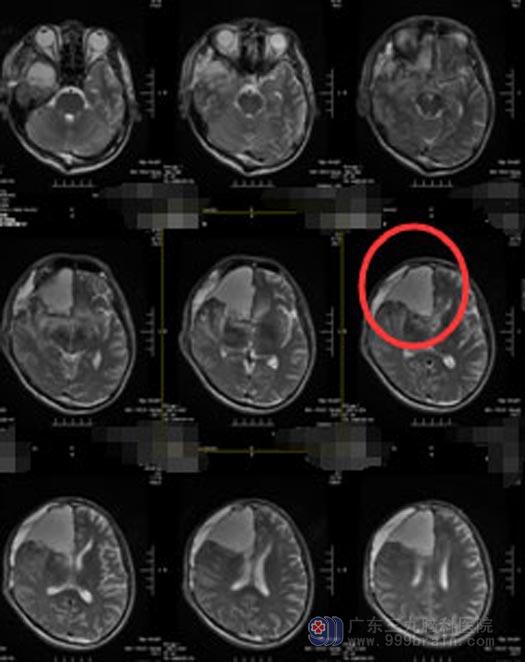

进一步MRI检查显示:右额颞岛叶-左侧额颞叶见不均匀异常信号影,大小约为65mm×45mm×71mm,边界模糊,诊断:.右额颞岛叶-左侧额颞叶弥漫性占位性病变,考虑高级别胶质瘤,以间变性星形细胞瘤可能性大。

脑功能区的肿瘤,常规手术难以彻底切除病灶,且容易损害脑功能区导致后遗症。为最大限度切除肿瘤并且最大限度保护患者功能,经家属同意后,由鲁明主任主刀,在唤醒麻醉下实施“右额颞岛叶、左额颞叶巨大占位性病变+硬脑膜修补术”。术前导航,利用神经电生理技术精确定位脑重要功能区,并探询病变与功能区的关系,在患者配合下顺利将肿瘤全切除。术后患者神志清醒,四肢肢体肌力V级,肌张力正常,术后病理:(右额颞岛叶、左额颞叶)胶质瘤,WHO III级。